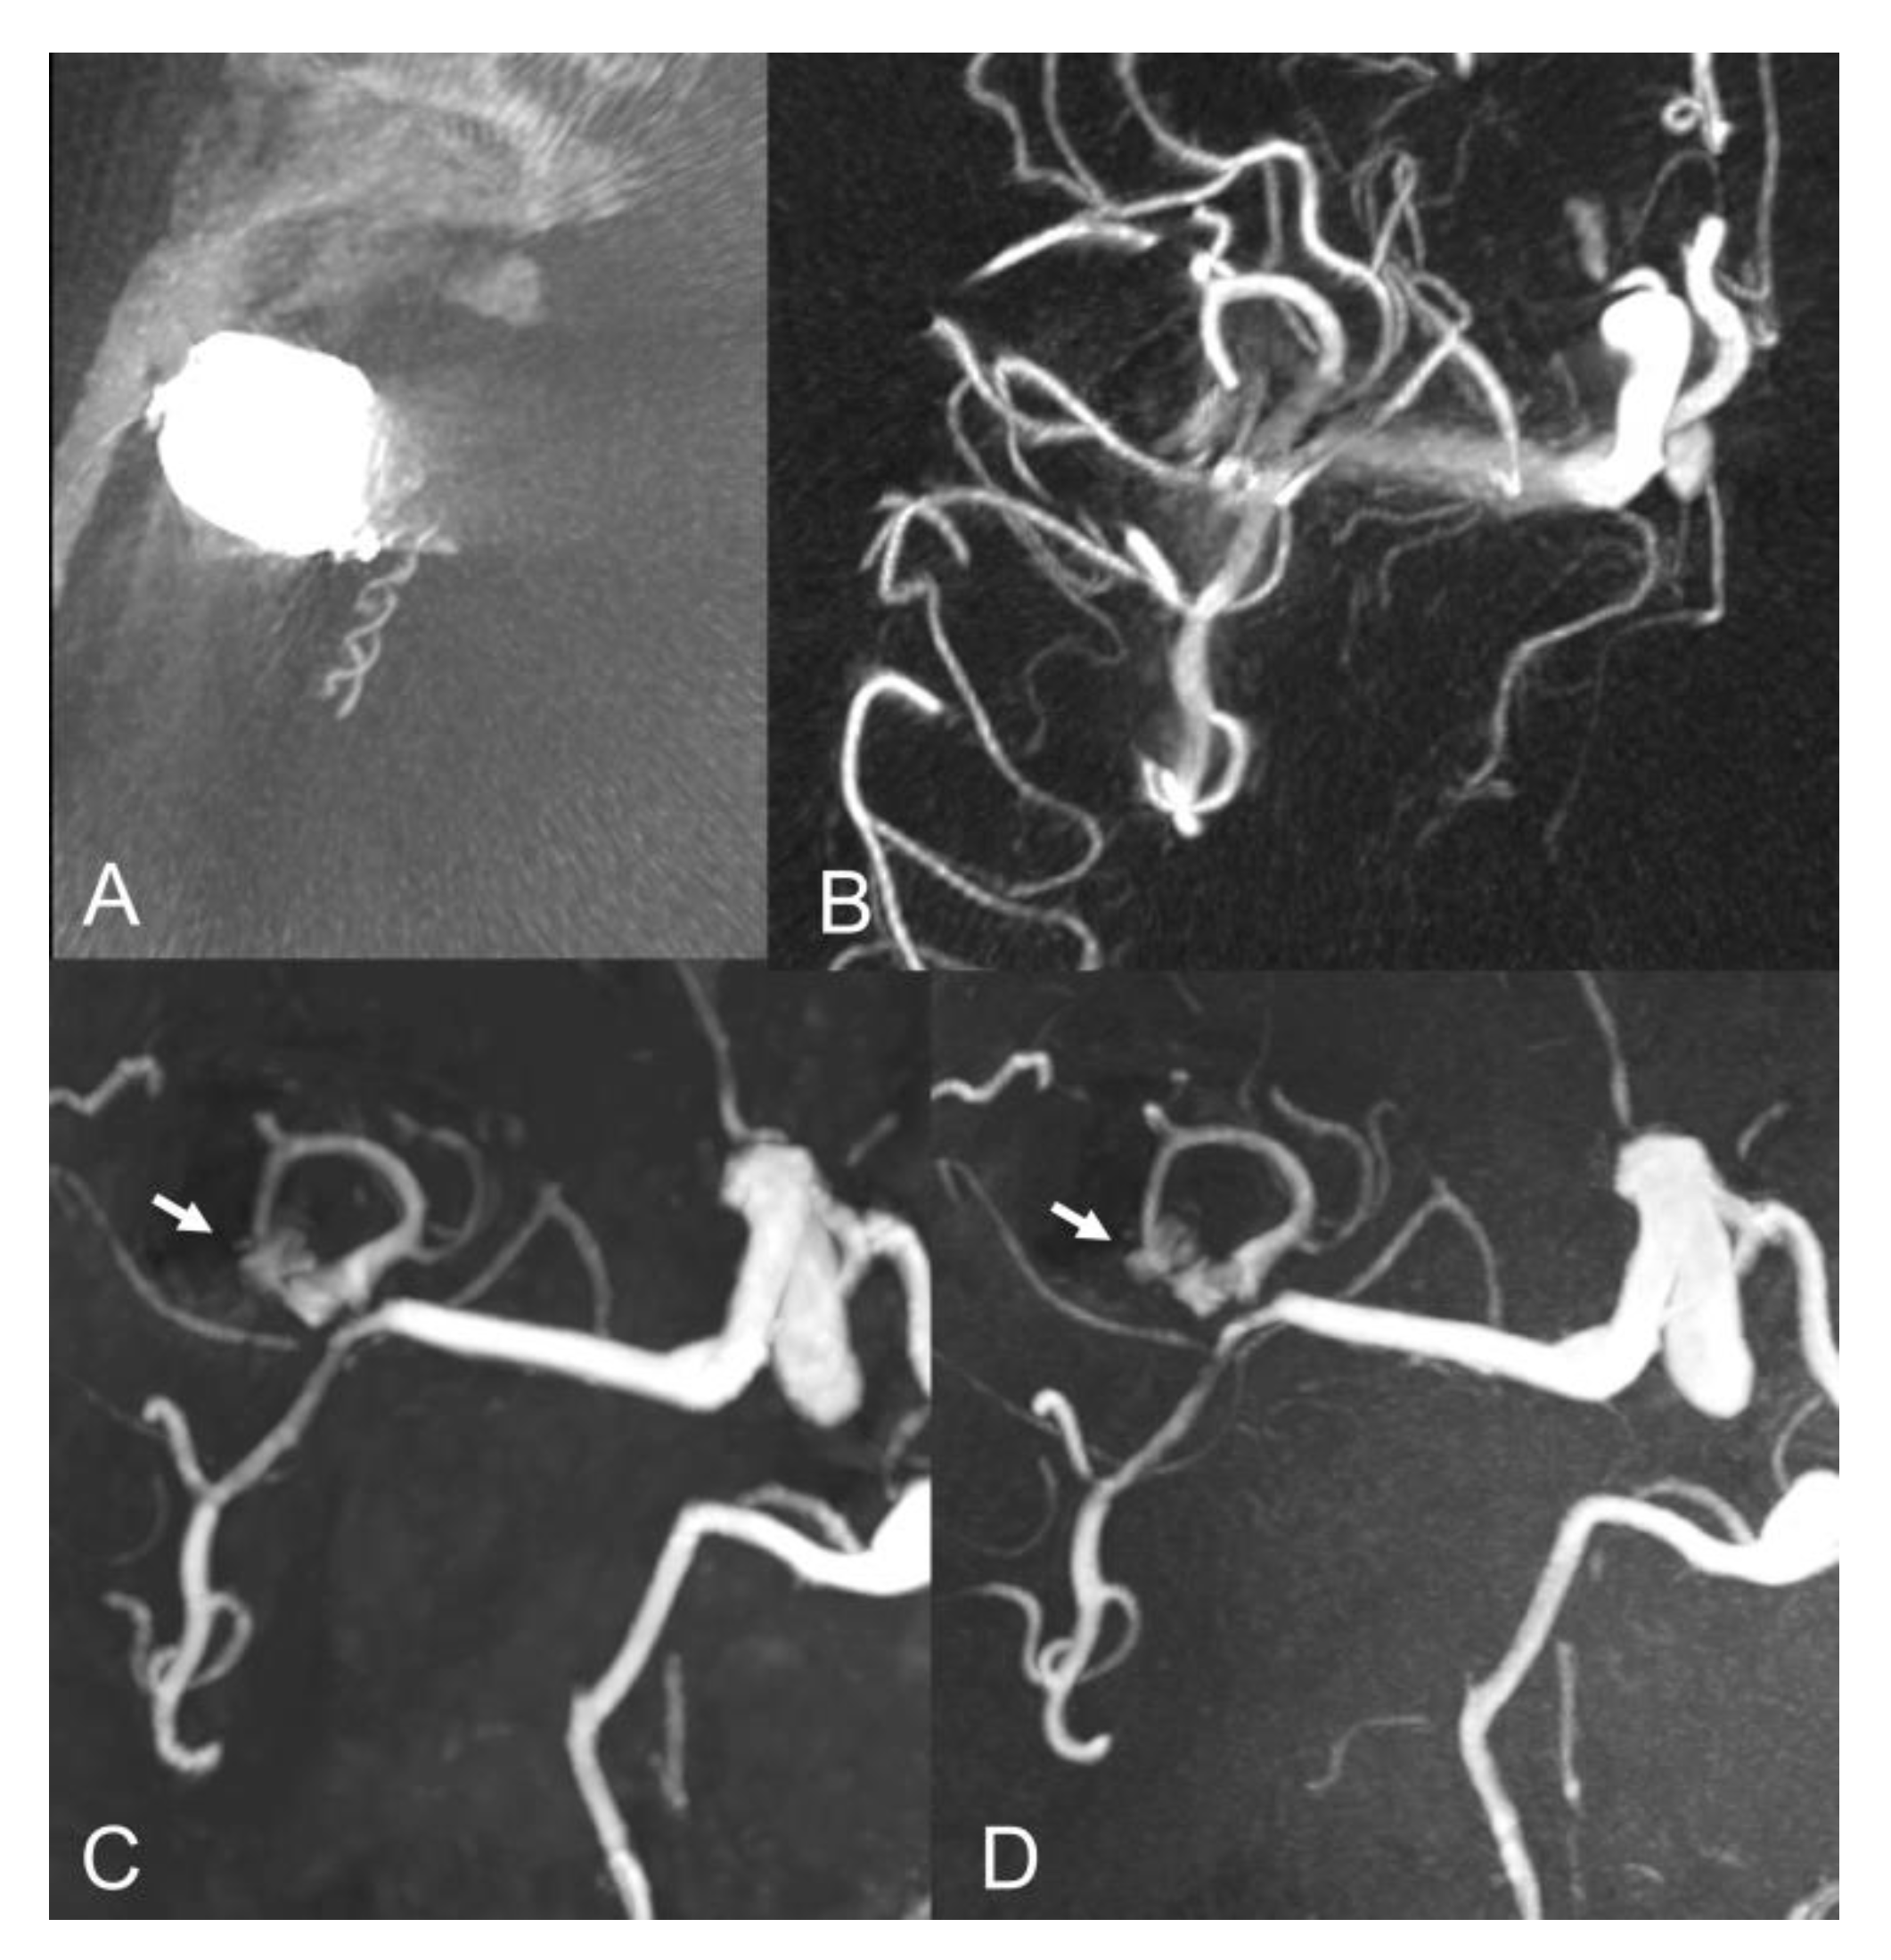

Figure 2.

Lateral view of internal carotid artery DSA before (A) and after (B) anterior communicating artery aneurysm coiling. Coronal MIP images of PI TOF (C) showing complete occlusion of the aneurysm (class I) and CS TOF (D) better depicting a tiny neck residue (arrow), which was nonetheless correctly graded as class II only by the interventional neuroradiologist.

The inter-modality agreement of CS and PI TOF MRA in the evaluation of aneurysm occlusion was perfect (κ = 1.00, p < 0.001) for all examiners except one, which classified one anterior communicating artery aneurysm as Class I on PI TOF images and as Class II on CS TOF images (Figure 2), leading, nonetheless, to an almost perfect inter-modality agreement (κ = 0.90, p < 0.001). The overall inter-modality agreement between the two techniques, considering all the readings by all the examiners (n = 88) was almost perfect (κ = 0.98, p < 0.001). No significant differences in inter-modality agreement were noted between patients who underwent coiling and stent-assisted coiling (κ = 1.00 and κ = 0.97, respectively). The overall inter-rater agreement was substantial (κ = 0.70, p < 0.001) and was almost identical for both CS TOF (κ = 0.71, p < 0.001) and PI TOF MRA (κ = 0.68, p < 0.001); 12 aneurysms (54.5%) were evaluated by all the examiners as completely occluded on both MRA techniques.

Our findings are in agreement with previous studies which showed comparable results between CS TOF and PI TOF MRA in the detection of a variety of cerebrovascular pathologies, including aneurysms, stenosis and arteriovenous shunts [21,22,23,24,25]. In particular, no significant differences were found between CS TOF and PI TOF MRA in the depiction of intact aneurysms, as well as in the measurement of neck, height and width of aneurysms [22]. In our study, only one case received a different occlusion classification in CS and PI TOF images, by the neurointerventionalist reader, who correctly appreciated a small neck remnant in CS TOF images, which was not apparent in the PI sequence (Figure 2). Therefore, while magnetic susceptibility artifacts due to the presence of the coil cast seem to have a comparable effect on both sequences in the majority of cases, we observed a sharper interface between blood flow and surrounding coils in some CS TOF images compared to PI TOF counterparts (Figure 1, Figure 2 and Figure 3).